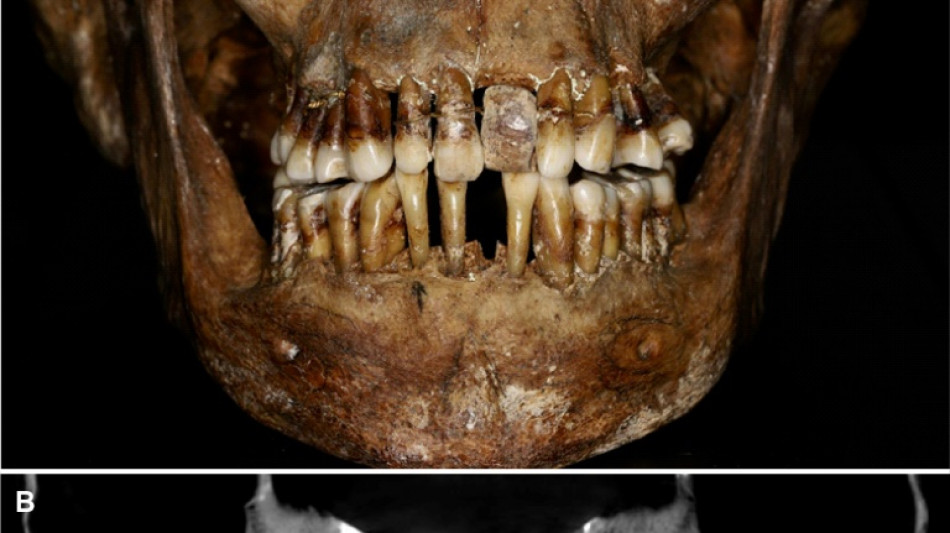

La dentition d'une aristocrate du XVIIe siècle comme marqueur social / Photo: Handout - INRAP/AFP

La sépulture d'Anne d'Alègre, morte en 1619 à l'âge de 54 ans, avait été déterrée lors d'une fouille au château de Laval, en 1988. Embaumé dans un cercueil de plomb, le squelette était particulièrement bien conservé, sa dentition aussi.

Plus de trente ans après, une équipe comprenant des archéologues et des dentistes dévoile qu'Anne d'Alègre était atteinte d'une maladie parodontale qui provoque le déchaussement progressif des dents, selon une étude parue cette semaine dans Journal of Archeological Science.

Les images radiologiques par "Cone Beam", un scanner en 3D, montrent que la patiente portait une prothèse dentaire remplaçant une incisive, soutenue par des fils d'or, ainsi qu'une ligature de contention sur des pré-molaires.

Des examens en macroscopie ont déterminé que cette prothèse était en ivoire d'éléphant, écartant la piste de l'ivoire de dents d'hippopotame, également utilisé à l'époque.

Ce traitement n'a fait "qu'aggraver la situation" de la patiente, explique à l'AFP Rozenn Colleter de l'Inrap (Institut national des recherches archéologiques préventives), auteure principale de l'étude.

A long terme, ce traitement, ainsi que les "multiples resserrages nécessaires, ont entraîné l'instabilité des dents voisines", détaille l'Inrap.

Les chercheurs suggèrent que l'objectif de ce traitement était thérapeutique, esthétique et surtout social, les femmes aristocrates se devant de garder une "apparence soignée". Ambroise Paré, médecin du roi et contemporain d'Anne d'Alègre, qui dessinait les mêmes types de prothèses, affirmait que "si un malade était édenté, sa parole était dépravée", souligne Rozenn Colleter.